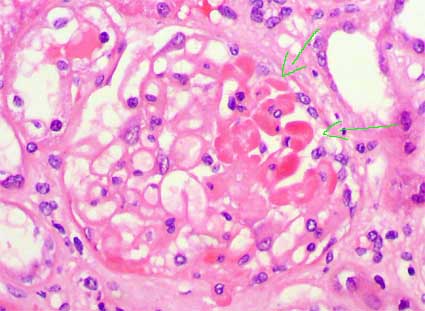

FSGS cellular variant

It is defined by the presence of at least one glomerulus with endocapillary hypercellularity involving at least 25% of the tuft and causing occlusion of the capillary lumen/lumina. Any segment may be affected. The endocapillary cells include endothelial cells, macrophages and foam cells. Also lymphocytes and polymorphous can be identified. The cells occasionally manifest apoptosis, producing pyknotic or karyorrhectic debris. Endocapillary fibrin occasionally is identified, but without associated rupture of the glomerular basement membrane (in these cases we must suspecting a necrotizing glomerulonephritis). Podocyte hypertrophy and hyperplasia are typically identified overlying these lesions, but are not required features

Exclusion of cases wit tip lesion is based on the observation that in many cases this lesion is cellular.

Figure 9. The arrows indicate a segment with increase of the cellularity and diminution or loss of the capillary lumina; the hypercellularity is due to proliferation of intrinsic glomerular cells and inflammatory cells that have migrated to the tuft, in this case mononuclear (lymphocytes and monocytes). Sometimes we can find polymorphous. In the case of the microphotography we found segmental and focal sclerosing lesions, NOS type, in 4 of 18 glomeruli, and only one (the one of the photo) with features of hypercellular variant. (H&E, X400)..